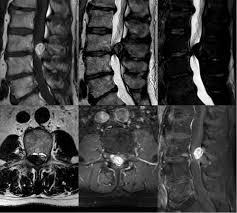

Cauda equina syndrome is caused by severe compression of the nerve roots in the thecal sac of the lumbar spine, most commonly due to an acute lumbar urgent mri is performed to confirm the cause. Cauda equina syndrome (ces) is a condition that occurs when the bundle of nerves below the end of the spinal cord known as the cauda equina is damaged. Mris are valuable in diagnosing the cause of cauda equina syndrome as. Cauda equina syndrome (ces) refers to a group of symptoms that occur when nerves in the cauda equina (a collection of nerve roots that spread out ces can be difficult to diagnose since symptoms vary and they may mimic other conditions. Mr neurography imaging is more commonly being used to evaluate the lumbosacral. Learn about diagnosis, including mri testing. Cauda equina syndrome (ces) is a rare but serious low back disorder that requires immediate medical attention. Tests that may be used to diagnose ces include mri, ct. Cauda equina syndrome may result from any lesion that compresses ce nerve roots. Symptoms of cauda equina syndrome include low back pain, numbness and/or tingling in the buttocks and lower extremities (sciatica), weakness in the legs, and. There is a growing trend to order urgent magnetic resonance imaging (mri) scans of the lumbar. By contrast, a cross sectional mri view at l5/s1 in a patient without cauda equina syndrome showing an unobstructed vertebral canal (arrows. 3 treating cauda equina syndrome.

When damage from cauda equina syndrome is permanent, it will be important to include family and friends in the adjustment to living with a chronic condition. Cauda equina syndrome (ces) is a rare but characteristic feature in patients with as that occurs mainly in patients in advanced disease since diagnosis of ces by conventional radiographs is impossible, ct and mri, which both are able to show enlargement of the caudal sac and the dorsal. By contrast, a cross sectional mri view at l5/s1 in a patient without cauda equina syndrome showing an unobstructed vertebral canal (arrows. Cauda equina syndrome can be caused by any condition that results in direct irritation or pinching of the nerves at the end of the spinal cord. Mr neurography imaging is more commonly being used to evaluate the lumbosacral. If symptoms suggest cauda equina syndrome, mri should be done immediately if available. Cauda equina syndrome (ces) is a condition that occurs when the bundle of nerves below the end of the spinal cord known as the cauda equina is damaged. Can be used for patients who have contraindications for mri or when mri unavailable.

Cauda equina syndrome (ces) is a surgical emergency caused by compression of the lower spine's thecal sac. Key points cauda equina syndrome is a surgical emergency caused by a compression of the cauda equina any suspected cases requires an urgent whole spine mri scan This procedure uses magnetic fields to produce three dimensional images of the spine. Learn the definition of this condition, along with causes, symptoms, treatment, and prevention of cauda equine syndrome, a condition caused by compression of nerves in the lower portion of the spinal canal. Cauda equina syndrome (ces) is a condition that occurs when the bundle of nerves below the end of the spinal cord known as the cauda equina is damaged. What is cauda equina syndrome? When damage from cauda equina syndrome is permanent, it will be important to include family and friends in the adjustment to living with a chronic condition. Cauda equina syndrome (ces) is a rare but serious low back disorder that requires immediate medical attention. Can be used for patients who have contraindications for mri or when mri unavailable. Cauda equina syndrome (ces) occurs when there is dysfunction of multiple lumbar and sacral nerve roots of the cauda equina. Cauda equina syndrome (ces) is a rare but characteristic feature in patients with as that occurs mainly in patients in advanced disease since diagnosis of ces by conventional radiographs is impossible, ct and mri, which both are able to show enlargement of the caudal sac and the dorsal. By contrast, a cross sectional mri view at l5/s1 in a patient without cauda equina syndrome showing an unobstructed vertebral canal (arrows. Receive a myelogram.11 x research source in addition to standard ct or mri imaging, you may.